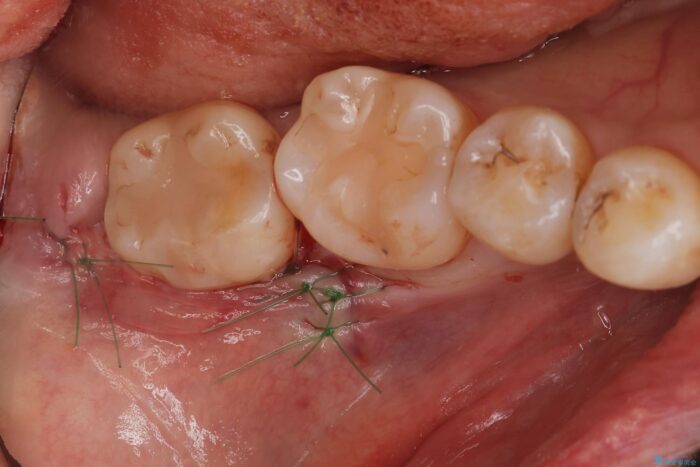

埋伏歯の抜歯

埋まっている親知らずを抜歯したいとご来院されました。

パノラマ,CT撮影を行い安全なことを確認して抜歯を行いました。

当日の抜歯も可能で、抜歯後1週間後に抜糸と消毒を行い処置は完了になります。